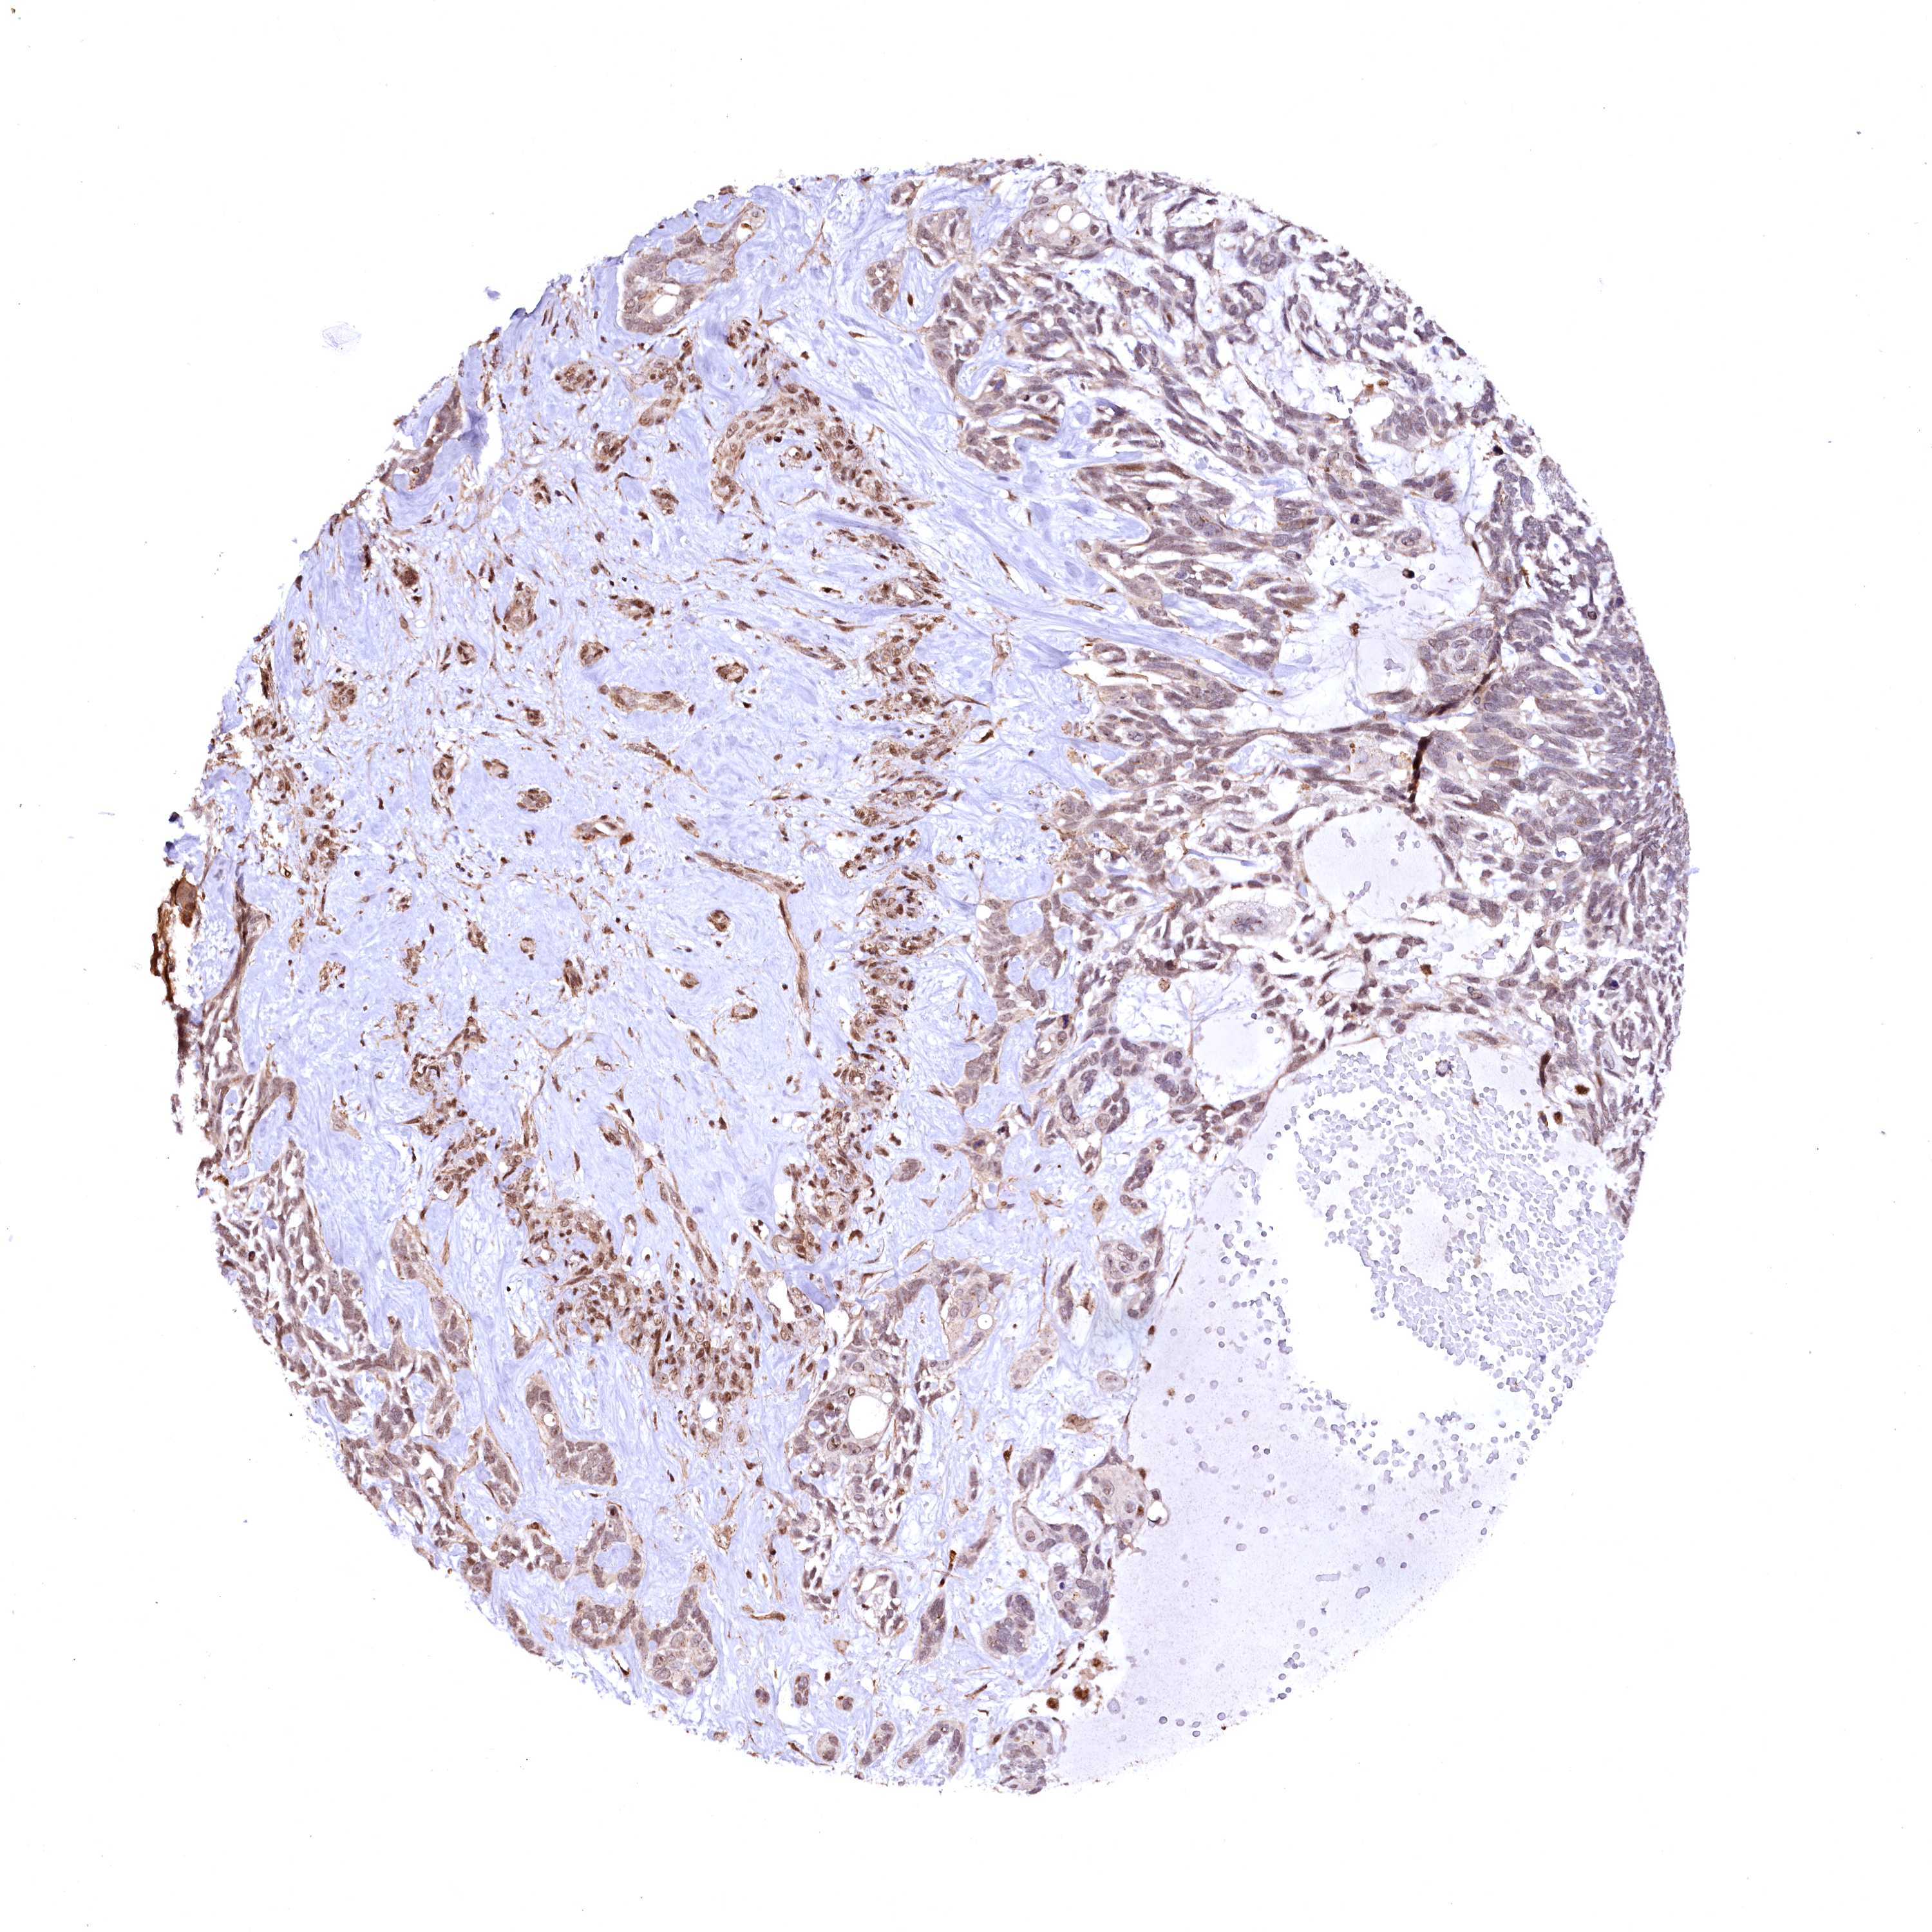

SKIN CANCER - Protein expressioni

A mouse-over function shows sample information and annotation data. Click on an image to view it in a full screen mode. Samples can be filtered based on level of antibody staining by selecting one or several of the following categories: high, medium, low and not detected. The assay and annotation is described here.

Antibody stainingi

Antibody staining in the annotated cell types in the current human tissue is reported as not detected, low, medium, or high, based on conventional immunohistochemistry profiling in selected tissues. This score is based on the combination of the staining intensity and fraction of stained cells.

Each image is clickable and will lead to virtual microscopy that enables deeper exploration of all samples and also displays staining intensity scores, fraction scores and subcellular localization as well as patient and tissue information for each sample.

Antibody HPA039513

Antibody HPA040015

Staining

High

Medium

Low

Not detected

Intensity

Strong

Moderate

Weak

Negative

Quantity

>75%

75%-25%

<25%

None

Location

Nuclear

Cytoplasmic/membranous

Cytoplasmic/membranous,nuclear

Basal cell carcinoma

Squamous cell carcinoma, NOS

Squamous cell carcinoma, metastatic, NOS